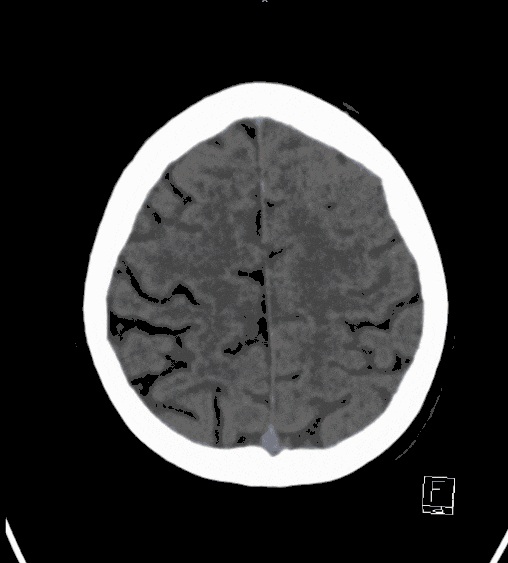

Cerebral hemorrhage (bloody stroke) always means an acute emergency situation for a patient and requires treatment in a specialized center. The exact cause must be determined. The most common cause is chronic high blood pressure. However, vascular malformations can also be considered as a cause.